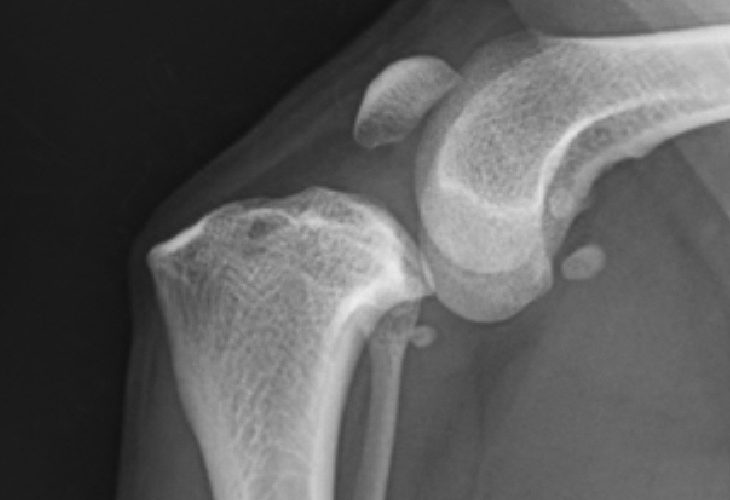

大腿骨骨折

膝蓋骨内方脱臼

大腿骨骨折+膝蓋骨内方脱臼整復